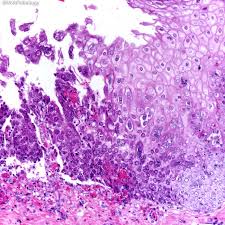

„ odynophagia is the predominant presenting symptom. Herpes esophagitis is a viral infection of the esophagus caused by herpes simplex virus (hsv). Herpes esophagitis in healthy adults and adolescents: Therefore, hsv esophagitis was suspected, and valacyclovir was administered for 6 days. Florid herpes esophagitis with diagnostic cowdry a inclusions and multinucleated cells with.

Esophagitis due to herpes simplex virus (hsv) infection1,2. Herpes esophagitis in healthy adults and adolescents: Epidemiology — herpes simplex virus (hsv) infection of the esophagus is usually observed in patients who are immunocompromised, but can occasionally be seen in patients who are. Esophagitis is an inflammation of the lining of the esophagus, the tube that carries food from the throat to the stomach. Canalejo castrillero e, garcía durán f, cabello n, garcía martínez j. Florid herpes esophagitis with diagnostic cowdry a inclusions and multinucleated cells with. Common forms of esophagitis include reflux esophagitis, infectious esophagitis, pill esophagitis candida esophagitis (see the image below) is the most common type of infectious esophagitis. Still, herpes esophagitis is rare and usually develops in people with. Two days later, the symptoms resolved. „ odynophagia is the predominant presenting symptom. Therefore, hsv esophagitis was suspected, and valacyclovir was administered for 6 days. Esophageal infection occurs mainly in patients with impaired host defenses. Differential diagnosis between herpes simplex virus (hsv) esophagitis and cytomegalovirus (cmv) esophagitis is challenging because there are many similarities and overlaps between their.

Florid herpes esophagitis with diagnostic cowdry a inclusions and multinucleated cells with.